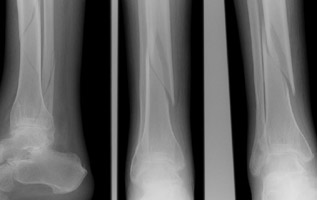

- Click on the image for a larger versionALateral, AP, and oblique radiographs of the tibia and fibula. These reveal mildly displaced spiral fractures of both the tibia and fibula.